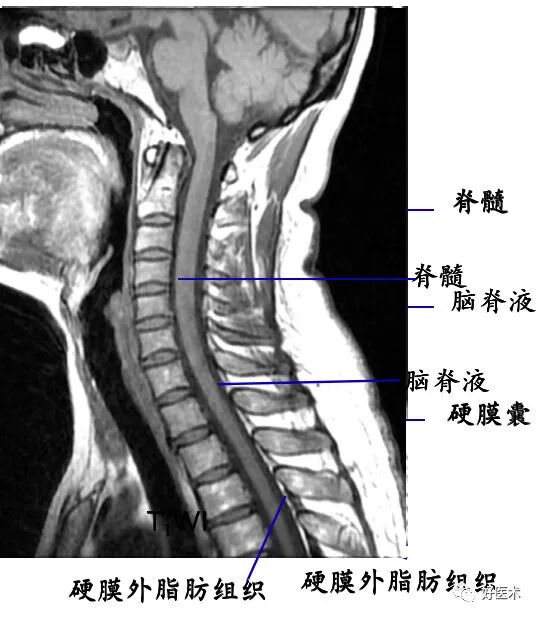

脊髓被膜及被膜间隙:

脊髓被膜(外→内):硬脊膜、蛛网膜和软脊膜

被膜间隙(外→内):硬膜外隙、硬膜下隙、蛛网膜下隙

4. 椎管及内容物

硬膜外脂肪:低密度影

硬脊膜囊:呈圆形或椭圆形软组织密度影。CT平扫不能区别硬脊膜囊、脑脊液和脊髓。

脊髓:位于椎管中心呈中等信号影

脑脊液:

T1WI上呈低信号;

T2WI上呈高信号影。

脊神经根:中等信号条状或圆点状影。

硬膜外脂肪组织:

T1WI上呈连续条状或带状高信号;

T2WI上呈中高信号。

椎内静脉丛:呈网状略低信号影。